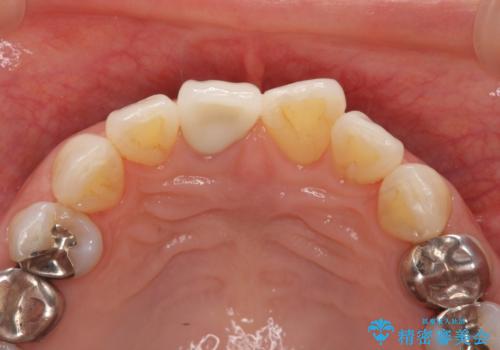

前歯の変色 セラミック審美補綴

- 前歯の変色の改善を希望され来院されました.

以前に神経が死に、根管治療を行った歯の変色が認められたためセラミックによる審美補綴治療を計画します。

- 16万円(仮歯・ファイバーコア・ジルコニアクラウンスペシャル)費用は治療当時の料金となります